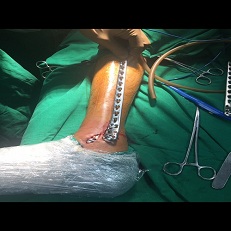

Minimal Invasive Tibia Plating And Fibula Nailing

Minimally Invasive Fracture Surgery